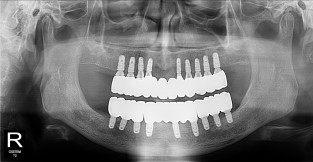

• 9

무치악

치료기간 : 2023-02-21 ~ 2023-10-21

1. 상기 x-ray 이미지 모두 동일한 해당 의료기관에서 진료한 환자입니다.

2. 상기 x-ray 이미지 모두 동일 인물의 것입니다.

3. 치료 전 이미지는 2023-02-21에 촬영했으며, 치료 후 이미지는 2023-10-21에 촬영하였습니다.

4. 상기 x-ray 이미지 모두 동일 조건에서 환자분의 동의를 받아촬영되었습니다.

* 임플란트 시술은 환자분의 상태(고혈압, 당뇨 등)에 따라 부작용이 있을 수 있으니, 반드시 전문의와 상담이 필요합니다.

* 임플란트 수술 부작용

: 수술 후 출혈, 교합, 통증, 붓기, 염증 등의 문제점이 발생할 수 있습니다.)